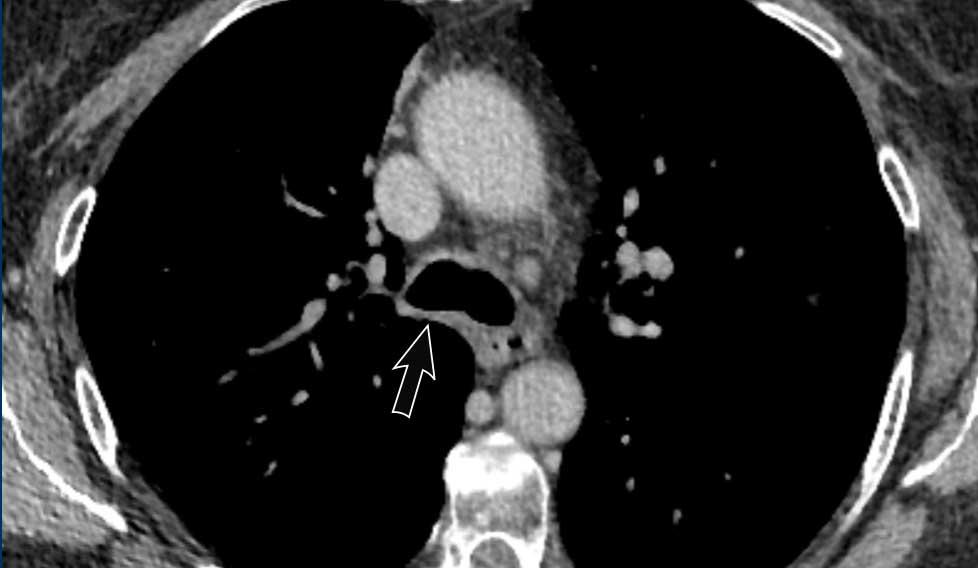

Hạch bạch huyết

Chèn ép phế quản chính phải do hạch bạch huyết to.